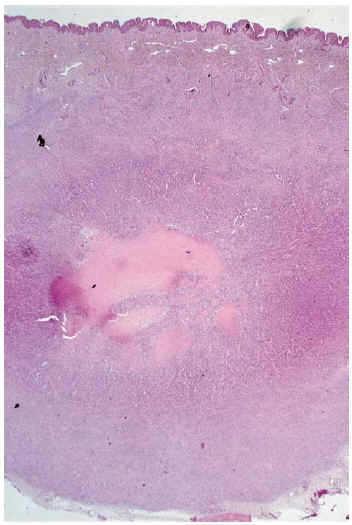

Se trata de una niña de 9 meses de edad sin antecedentes personales de interés. Presentaba desde los 4 meses de edad una lesión nodular, de 2 cm de diámetro máximo, situada en región deltoidea posterior izquierda. La lesión era de superficie lisa, eritematoviolácea, dura e infiltrada, pero desplazable sobre planos profundos (fig. 1). La lesión había aumentado progresivamente de tamaño hasta 2 meses antes de la consulta, en que parecía haberse estabilizado. Se extirpó quirúrgicamente.

Fig. 1.--Lesión nodular infiltrada de 2 cm en región deltoidea posterior izquierda.